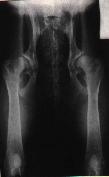

Na levém snímku můžeme vidět kyčelní klouby zdravého

zvířete, ale na druhém snímku je zrentgenované zvíře postižené těžkou

dysplazií.